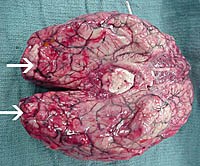

Các xét nghiệm về mặt mô học

Sinh thiết và các mẫu bệnh phẩm khi phẩu tích tử thi từ các bệnh nhân mắc PAM biểu hiện viêm mạnh, với sự xâm nhập các bạch cầu đa nhân trung tính, xuất huyết và hình ảnh hoại tử đặc trưng của viêm màng não cấp. Các kháng thể huỳnh quang có thể giúp xác định nhiều thể tư dưỡng trong mẫu dịch não tủy.